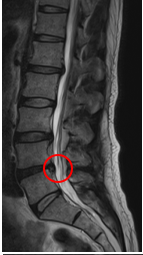

診察と検査結果

この患者様は赤い枠で示されている箇所に椎間板ヘルニア(L4/5)が認められます。